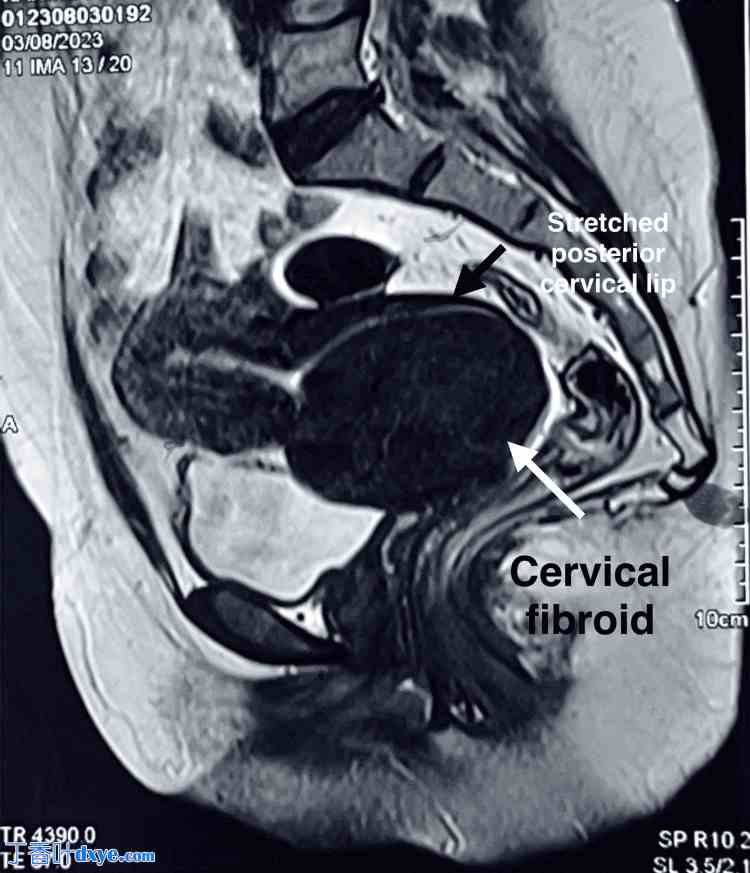

一般体格检查发现患者面色苍白。实验室检查显示血红蛋白水平为 4.1 g/dL,脉搏 110 次/分,收缩压 86 mmHg。MRI 显示子宫大小为 6.3 x 7.6 cm,子宫下段可见一个 10 x 10 cm 的异质性肿块,提示为子宫肌瘤,如图 12 所示。双侧附件未见异常。

图 12. MRI 显示子宫大小为 6.3 x 7.6 cm,子宫下段可见一个 10 x 10 cm 的异质性肿块,提示为宫颈肌瘤。